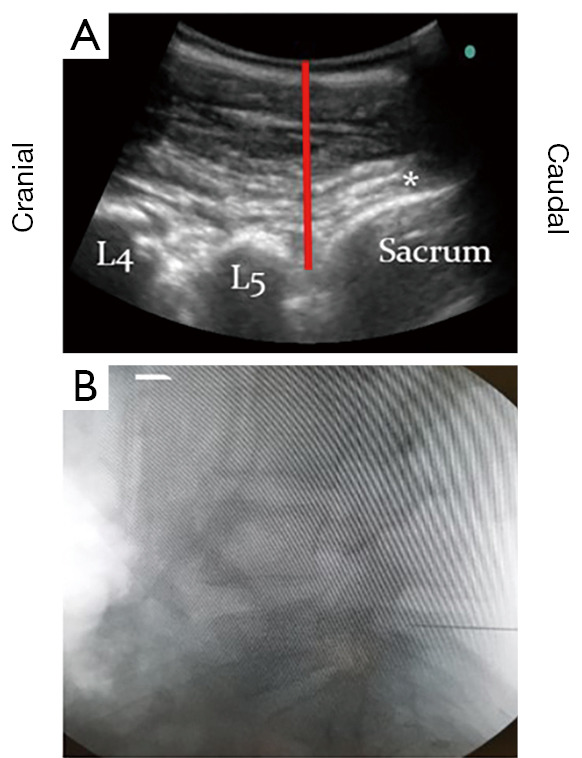

Lumbar spinal surgery relies on palpation of anatomical landmarks and X-ray imaging confirmation to identify the correct spinal level, therefore exposing patients and staff to radiation, and increasing intraoperative time and cost. Ultrasound (US) assistance is being used to visualise spinal anatomy by many specialities, such as neurology and anaesthetics, and can be used intraoperatively in selected spinal surgery cases. However, its potential use to check spinal levels prior to surgery remains understudied. This prospective, pilot study screened all patients requiring a primary elective or emergency lumbar discectomy, under the supervision of a single consultant neurosurgeon, over an 8-month period at a single neurosurgical unit. US assistance was used to identify and mark the proposed spinal level prior to skin incision. The resemblance of the parasagittal lumbar US images to the back of the dinosaur Stegosaurus aided users in identifying the relevant anatomical structures necessary to mark the desired spinal level, (e.g., lumbar laminae, intervertebral spaces, sacrum). This inspired our description of the US images of the lumbar spine as 'The Stegosaurus Appearance'. The spinal level marked by US was then confirmed in the standard fashion using intraoperative X-ray imaging. In 100% of cases (12/12), the desired spinal level was correctly identified using US, confirmed by the subsequent intraoperative X-ray images. US assistance appears to be a safe, quick, and accurate tool for identifying the correct lumbar spinal level prior to skin incision, and could therefore represent a useful adjunct to supplement level checking in lumbar spinal surgery.